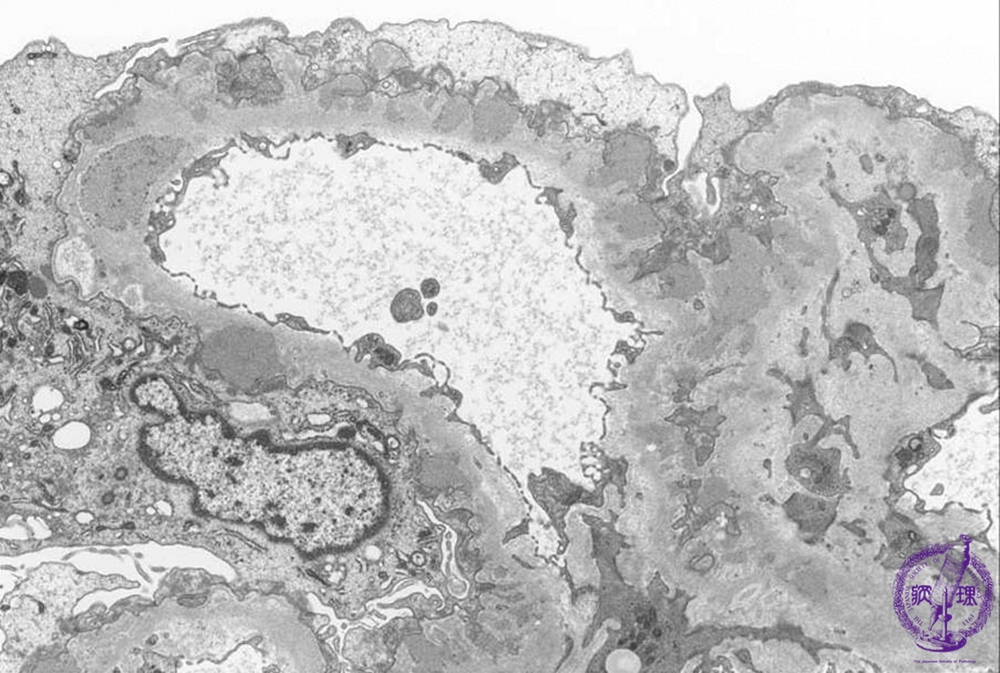

- ★(2)Membranous nephropathy

Electron microscopic findings: Stage II (focally Stage III). The number and size of electron dense subepithelial deposits (red arrows) are increased and spikes are seen forming between deposits (dotted blue line).